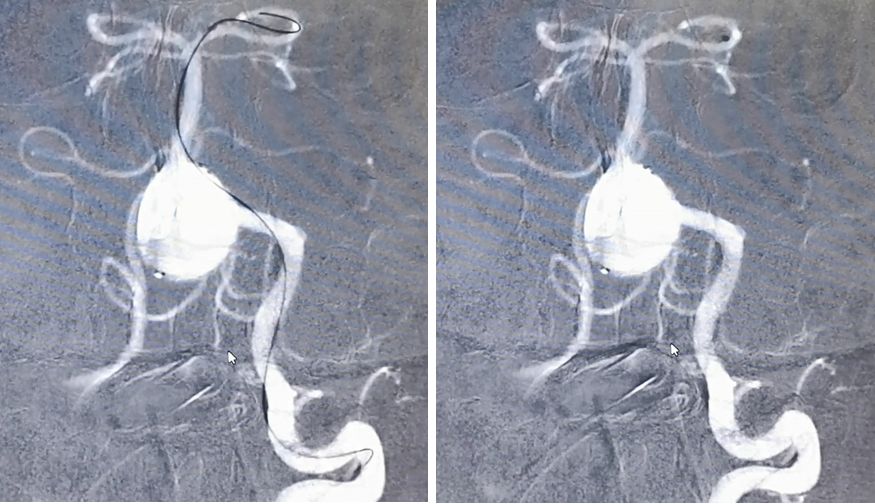

经左椎动脉造影可见椎-基底动脉汇合部巨大动脉瘤,双侧椎动脉均有累及,以左侧椎动脉为主,右侧PICA与动脉瘤有一定距离,基底动脉稍受累及,AICA距离动脉瘤较近。

先用Synchro-200携Echelon-10由右椎动脉进入动脉瘤腔,微导管在瘤腔内盘圈,可以在输送弹簧圈的时候使弹簧圈分布更均匀

然后将Marksman微导管通过左侧椎动脉顺利进入左侧大脑后动脉

PED支架沿Marksman进入准备释放

释放PED。由于瘤颈很宽,所以PED需要足够长,动脉瘤远端和近端才能具有足够的锚定力量,防止支架坠入瘤腔内。所以,我们选择了3.25*35mm的支架。支架上端定位在基底动脉中段

PED释放完毕,位置及贴壁良好,左椎-基底动脉血运通畅,未填弹簧圈,即可见到瘤腔内造影剂的滞留,说明支架贴壁良好,起到了良好的重建作用